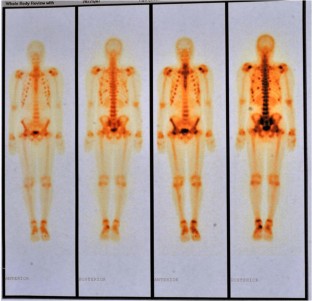

Fig. 1